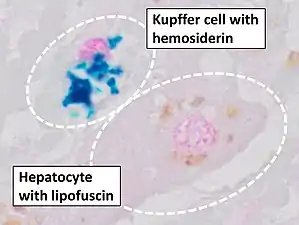

Stain for iron

Prussian blue is a common histopathology stain used by pathologists to detect the presence of iron in biopsy specimens, such as in bone marrow samples. The original stain formula, known historically (1867) as "Perls Prussian blue" after its inventor, German pathologist Max Perls (1843–1881), used separate solutions of potassium ferrocyanide and acid to stain tissue (these are now used combined, just before staining). Iron deposits in tissue then form the purple Prussian blue dye in place, and are visualized as blue or purple deposits.[39]

Histopathology of the liver, showing a Kupffer cells with significant hemosiderin deposition next to a hepatocyte with lipofuscin pigment. H&E stain.

Histopathology of the liver, showing a Kupffer cells with significant hemosiderin deposition next to a hepatocyte with lipofuscin pigment. H&E stain. Prussian blue staining, highlighting the hemosiderin pigment as blue.

Prussian blue staining, highlighting the hemosiderin pigment as blue. Prussian blue stain

Prussian blue stain